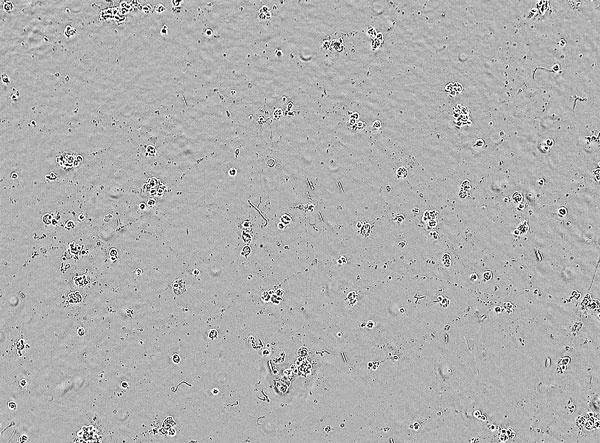

ALSモデル (運動神経細胞 × 酸化ストレス)

ALSモデルとなり得る酸化ストレスによる神経傷害の系を用いて、化合物評価が可能です。

独自の酸化

ストレス誘導法-

酸化ストレスなし